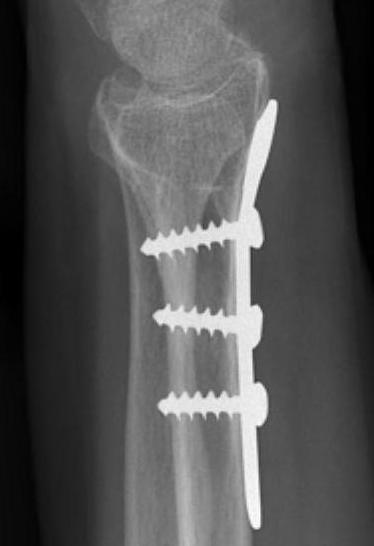

ORIF with locking plates

Advantages

Accurate restoration of intra-articular anatomy

Stable fixation with early mobilisation

Fragment specific plates

| Volar locking plates | Volar rim plates | Radial styloid plates |

Volar locking plate technique

AO surgery modified Henry to distal forearm

Vumedi volar locking plate distal radius

Bed of FCR approach

- incision over FCR and mobilize ulnarly

- divide fascia in bed of FCR and retract radial artery laterally

- L shaped released of pronator quadratus

- cannot make volar capsulotomy - divides radiocarpal ligaments and causes instability

- elevate 1st extensor compartment (APL / EPB)

- release brachioradialis from radial styloid

Reduce fragments and temporarily stabilize with K wires

- apply volar plate with screw fixation in scaphoid and lunate fragments

- ensure not beyond watershed line to avoid flexor tendon irritation / rupture

- engage dorsal cortex but not too long to prevent EPL rupture

- on lateral, raise hand 30o to view joint

- +/- radial styloid plate if required